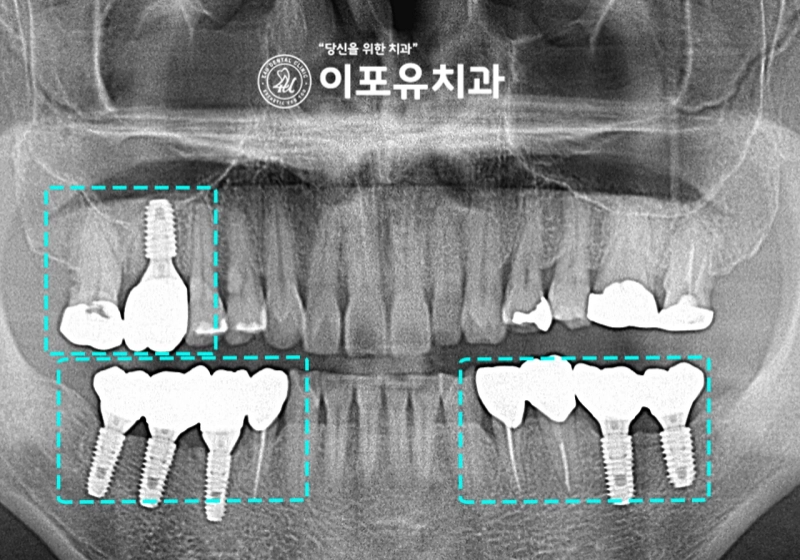

앞서 설명드렸듯이 치조골이 모자란 곳은

골이식을 동반하여 식립을 해야되는데요.

골 유착이 충분히 일어난 것을 확인한 뒤에

크라운 제작을 위한 픽업 인상까지 채득을 하게 됩니다.

“완성된 보철의 모습을 함께 볼까요?“

이전과는 달리 심미, 기능적으로 개선된

지르코니아 크라운을 확인할 수 있습니다.